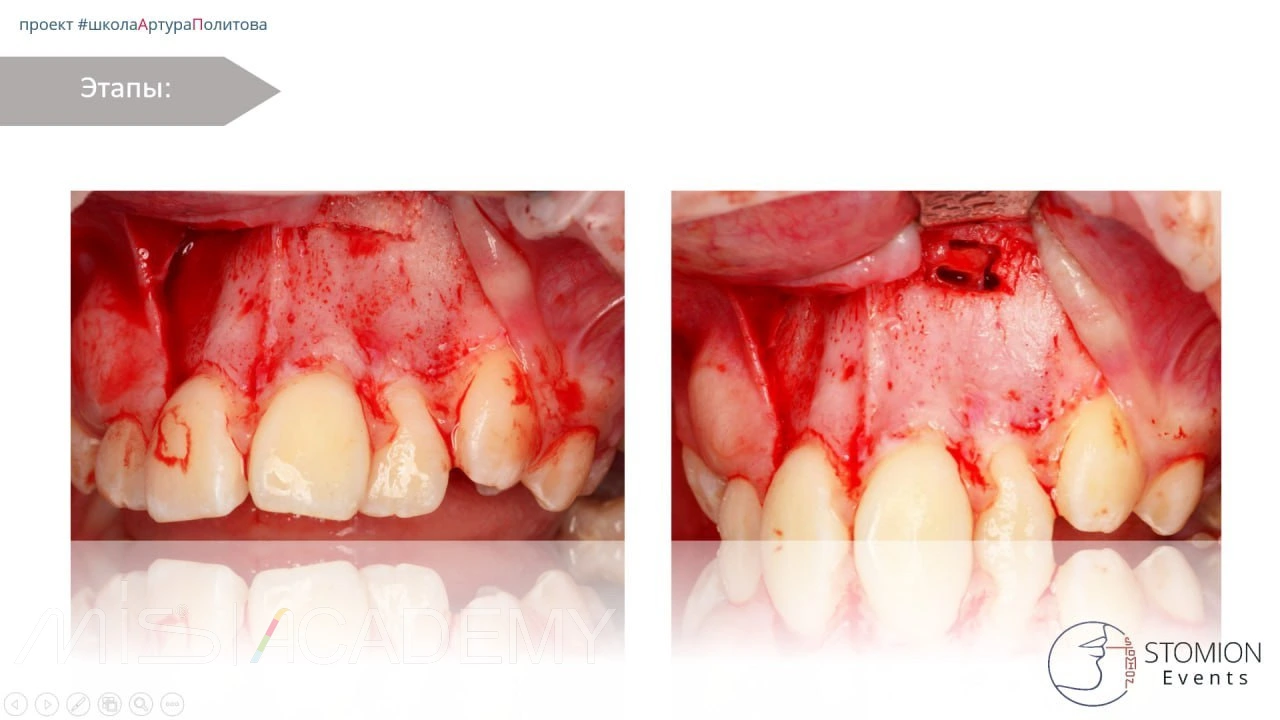

— Трепанация в области истонченного кортикала, чтобы не травмировать сосудистонервный пучок.

— Сегментация.

— Извлечение центральной части коронки, далее бугра, далее смещение зуба в просвет и сегментация по типу шинковки до полной экстракции.